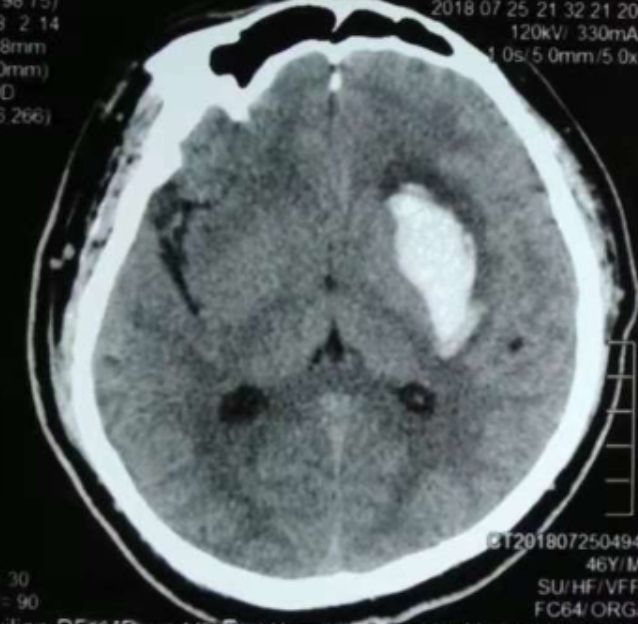

3個(gè)月前CT:腦出血

術(shù)前CT:血腫已經(jīng)液化,但仍有占位效應(yīng)